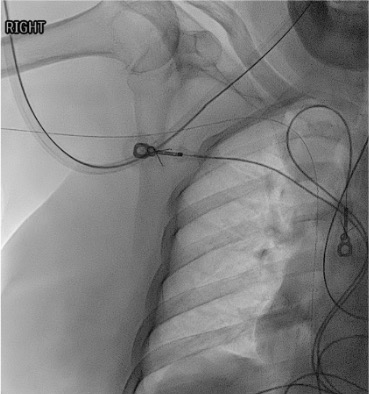

View wire in IVC

Fluoroscopy showing PICC wire looped in IVC confirming venous position